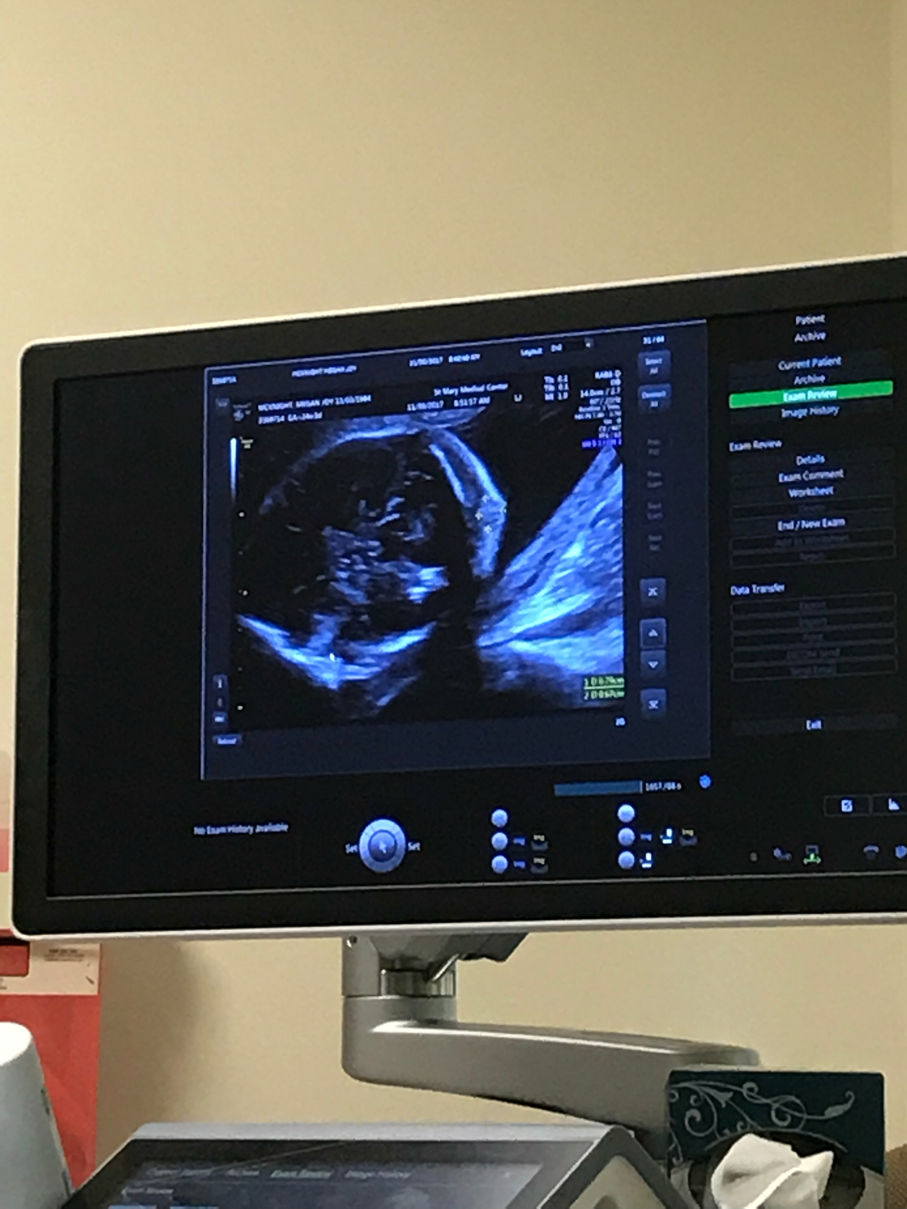

Bump update (24 weeks 3 days)

Baby’s head bump shrunk! It’s now less than 1 cm. The technician at the perinatal specialist said if today were the anatomy scan she wouldn’t even have said anything. She had to look really hard to find it. We go back in four weeks to watch it “shrivel up and go away” She also checked the heart, brain, stomach, etc while we were there. Everything looks good!

Baby was dramatic and had two hands in front of his/her face. The one picture looks like a three toed sloth! It’s awesome!!! (The baby has five fingers on each hand)

I’ll work on a picture of Meg’s belly this weekend. For now, here are pictures of baby M!